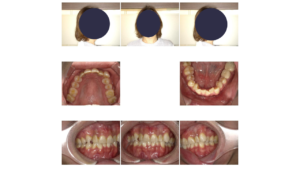

次に、最新のデジタル機器を用いて、今のお口と体の現状を「見える化」します。

・3Dスキャン(iTeroなど): 従来の型取りの苦しさはありません。数分でお口を立体的に再現します。

・レントゲン・顔貌写真: 歯の根っこの状態はもちろん、顎の関節の形を詳しく見ます。20代の頃に「顎がパキパキ鳴っていた」という経験はありませんか? それは、顎のクッション(関節円板)がズレ始めたサインです。